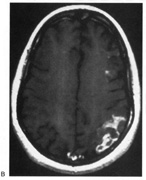

Fig. 18. Magnetic resonance imaging scan of patient with stroke causing a right hemiachromatopsia as well as partial superior quadrantanopia.

Achromatopsia in the contralateral hemifield alone can follow unilateral right or left occipital lesions (Fig. 18). Patients are typically asymptomatic until the defect is demonstrated on examination.234,235 Hemiachromatopsia is usually associated with a superior quadrantanopia;234,235,241 therefore, the color defect is only demonstrable in the remaining inferior quadrant. The preserved color vision in the ipsilateral hemifield allows normal or near-normal performance on centrally viewed tests of color vision such as pseudoisochromatic plates. The incidence of hemiachromatopsia is probably underestimated, given its asymptomatic nature and the failure of routine clinical color tests to detect its presence.

HEMIACHROMATOPSIA.